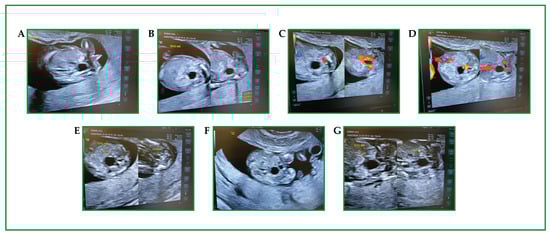

2. Case Report